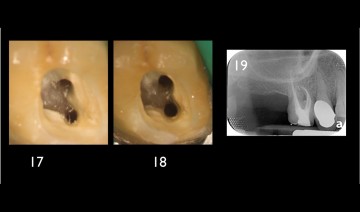

Initial x-ray, opening of the access cavity and x-ray with scouting file in the MB1 and MB2. The mineralization of the root canal entrance constrains the initial scouting.

The flaring instrument One Flare eliminates the first millimeters of the pulp parenchyma, thus reducing the stress on the files which are realigned in the root canal, in order to facilitate the access to and the shaping at the apical preparation limit.

The reasoned preparation of the root canal entrance with the flaring instrument One Flare allows for safe endodontic shaping and cleaning while preserving the root canal’s homothety.